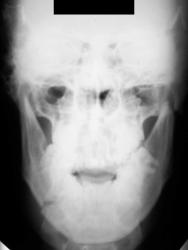

Вот один из них.

Валентин Львович! Результат налицо. Открытый перелом в области 8-го зуба. И на противоположной стороне в области 2-3-го зубов.

Переломы: через лунку 8 с одной стороны, с другой - в обл 3/4.

Замечания: не маркирована сторона, не достаточно косой снимок - наложение сторон. Стоило снять с двух сторон.